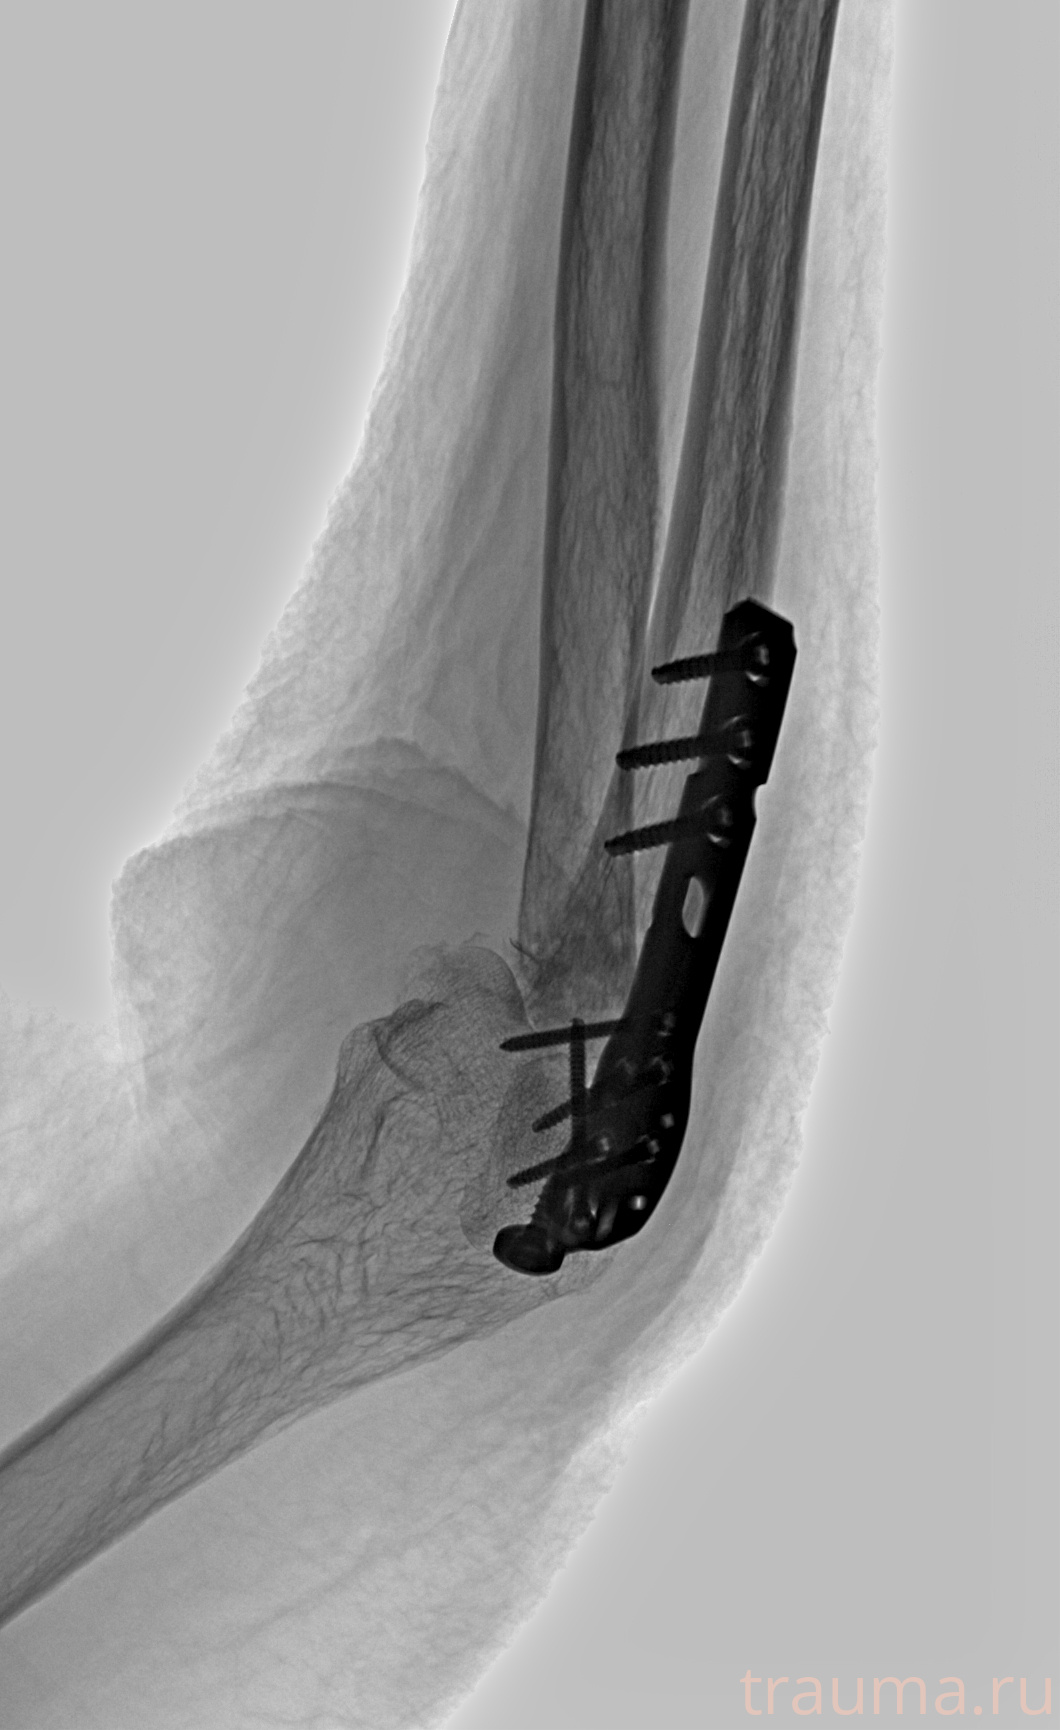

Рентгенограммы